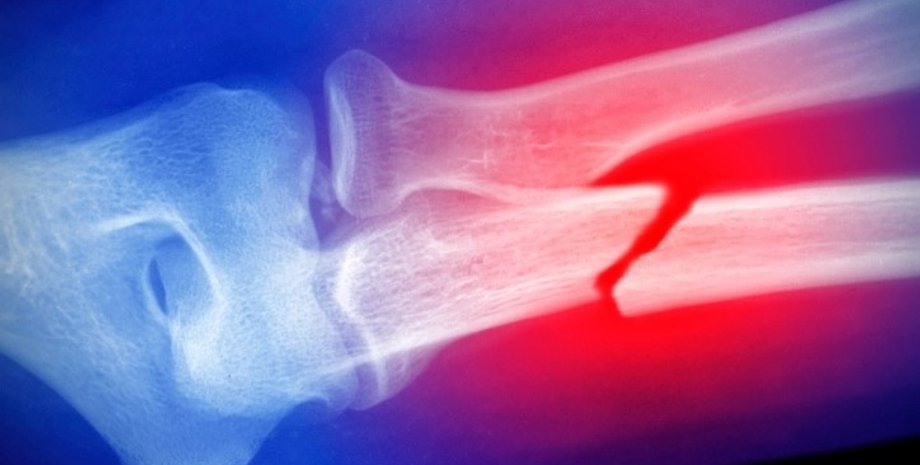

Множественные переломы в детстве могут быть "опасным звоночком" | Фото: Getty Images

Новое исследование полагает, что сломанные кости в детстве могут быт "предупредительными звоночками" остеопороза и будущих переломов в более взрослом возрасте.